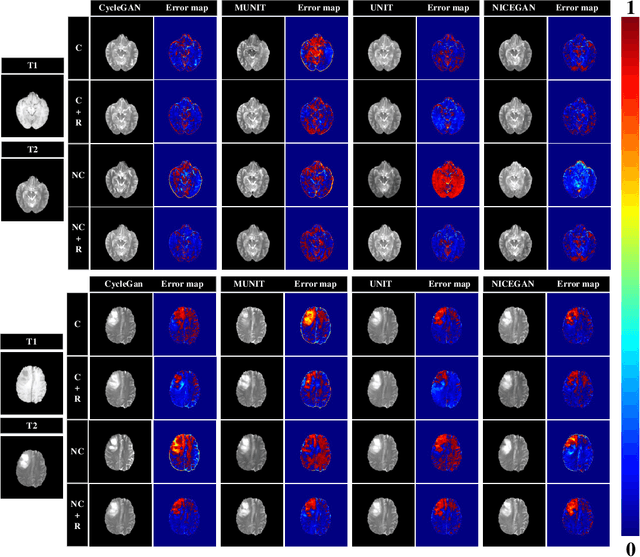

Abstract:Supervised Pix2Pix and unsupervised Cycle-consistency are two modes that dominate the field of medical image-to-image translation. However, neither modes are ideal. The Pix2Pix mode has excellent performance. But it requires paired and well pixel-wise aligned images, which may not always be achievable due to respiratory motion or anatomy change between times that paired images are acquired. The Cycle-consistency mode is less stringent with training data and works well on unpaired or misaligned images. But its performance may not be optimal. In order to break the dilemma of the existing modes, we propose a new unsupervised mode called RegGAN for medical image-to-image translation. It is based on the theory of "loss-correction". In RegGAN, the misaligned target images are considered as noisy labels and the generator is trained with an additional registration network to fit the misaligned noise distribution adaptively. The goal is to search for the common optimal solution to both image-to-image translation and registration tasks. We incorporated RegGAN into a few state-of-the-art image-to-image translation methods and demonstrated that RegGAN could be easily combined with these methods to improve their performances. Such as a simple CycleGAN in our mode surpasses latest NICEGAN even though using less network parameters. Based on our results, RegGAN outperformed both Pix2Pix on aligned data and Cycle-consistency on misaligned or unpaired data. RegGAN is insensitive to noises which makes it a better choice for a wide range of scenarios, especially for medical image-to-image translation tasks in which well pixel-wise aligned data are not available